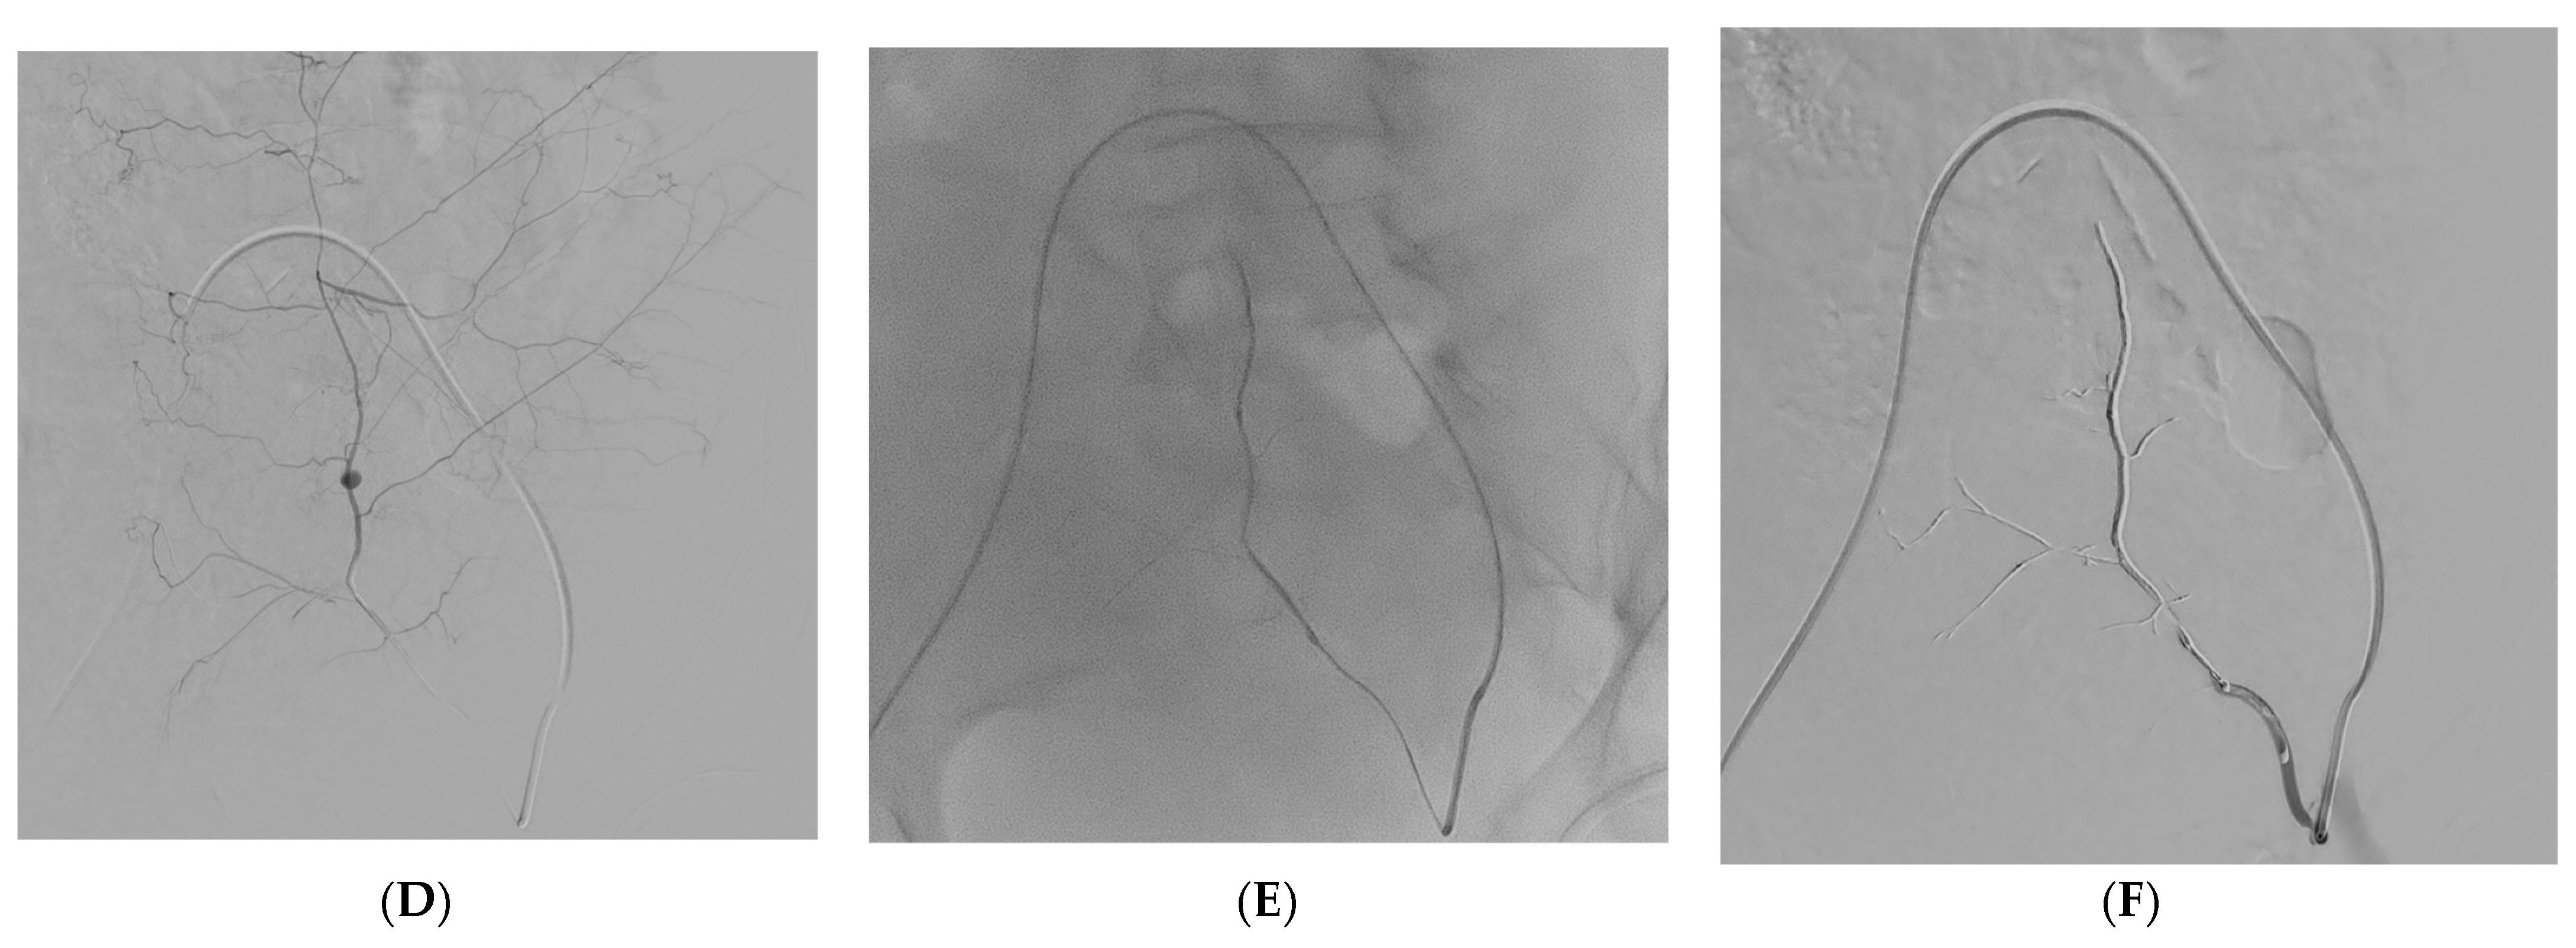

Figure 2. A 57-year-old man with coagulopathy, COVID-19, abdominal pain, and acute anaemia. (AC) CT angiography demonstrating a rectus sheath hematoma with a pseudoaneurysm of the left inferior epigastric artery depicted in the oblique sagittal and coronal planes by maximum intensity projection reformatting. (D) Digital Subtraction Angiography showing selective catheterization and pseudoaneurysm of the inferior epigastric artery. (E,F) Fluoroscopy showing the Onyx 34 cast distributed along the inferior epigastric artery and Digital Subtraction Angiography confirming successful embolization.